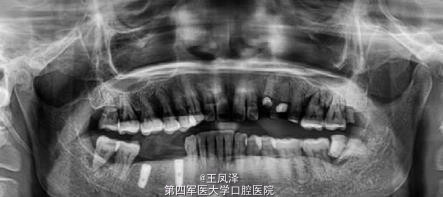

患者,男,59岁,要求做固定修复。44#/45#/46.残根,通过交流沟通选择种植。今天复诊残根拔除3周,要求尽快种植。查软组织愈合不全,但无炎症。告知理论上讲即刻延期需4-6周为好。同意签手术同意书,局麻消毒准备种植。